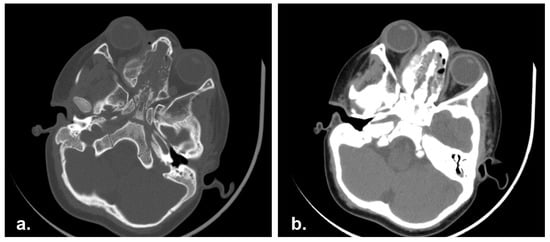

A 3 years-old male referred to Pediatric Oncology in January 2014 complaining of superior eyelid edema and bilateral exophtalmus. The patient was in good general condition. The MRI study showed a naso-ethmoidal mass with intraorbital extension. There were also bony defects in the right medial orbital wall and floor. Additionally, the contralateral orbit was also partly involved (Figure 4).

Figure 4. Pre-operative Computed Tomography scan (CT) showing an ethmoidal mass involving the nasal septum and bilateral lamina papyracea. (a) Bone and (b) soft tissue CT algorithm.